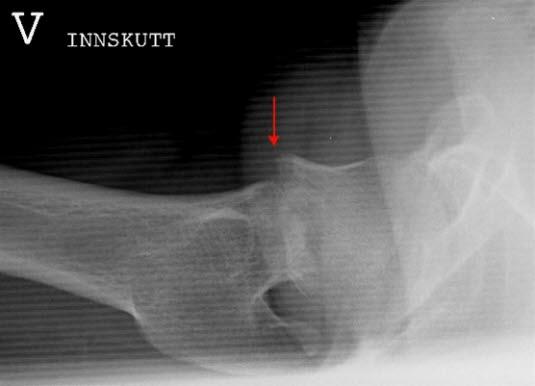

Ikke alle brudd fører til knekkdannelse mellom de to bruddendene. Det hender også at bruddet fører til at de to beinendene stukes sammen (innkilte brudd) slik at bruddet er forholdsvis stabilt og ikke kommer ut av stilling. Slike brudd kan være vanskelige å se på røntgen.

Det hender at røntgenbildet av hofta er normalt, selv om det foreligger et brudd. Det skjer av og til ved de innkilte bruddene. Ved sterk mistanke om hoftebrudd, men normalt røntgen, tas det MR- eller CT-bilde. Eventuelt tas nytt røntgenbilde en uke senere.